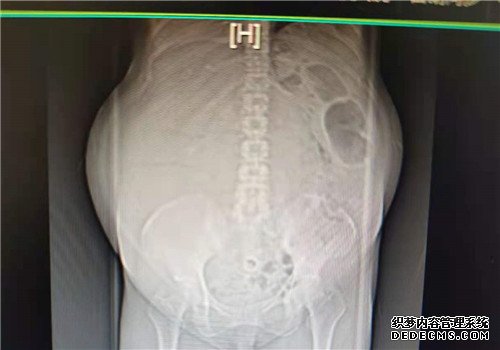

术前影像图,肚子形状如“蛙状腹”

直到一个多月前,刘女士因长达半个月时间的胸闷,来到了重医附二院江南院区就诊。医生为其做了腹部彩超,发现腹腔内有一巨大包块,“包块从上到下占据了大半个腹腔,把她的肚子都撑得鼓鼓的”。医生根据经验判断该包块可能来源于肾脏,于是将刘女士转入泌尿外科住院治疗。

“住院之后,我们对她进行了进一步的检查,做了全腹部的增强CT。”泌尿外科徐光勇教授回忆说,CT结果显示该巨大包块最大截面约有274*192mm,来源于右肾,可能是血管平滑肌脂肪瘤。

“泌尿外科的肿瘤分为很多种,但无论哪一种一般在3-4公分的时候便能发现,能长到如此巨大实属罕见,可以说是我们开科以来遇到最大的一个。”徐光勇教授说,肿瘤能长这么大一般需要几年的时间,而导致这么长时间都没有发现肿瘤的原因,一方面是刘女士健康意识的缺乏,没有定期参加体检,另一方面是因为肿瘤的生长是一个循序渐进的过程,刘女士一直以来也并没有觉得身体有何不适。